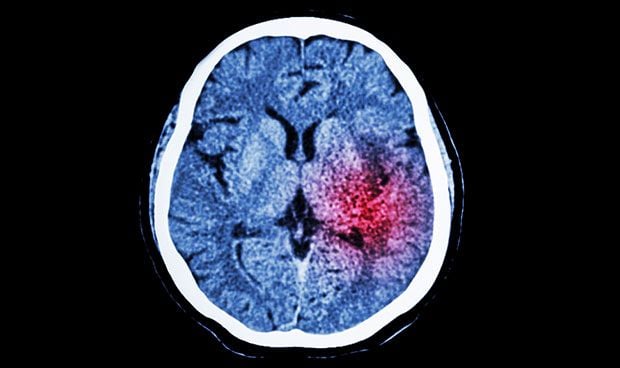

Imagen obtenido por TAC de un ictus isquémico.